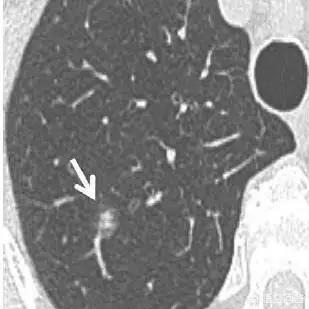

Apropos Knoten: Betrachten wir zunächst einen Fall von kleinen Knoten in der Lunge. Der Patient war erkältet und hustete, und bei einer CT-Untersuchung des Brustkorbs wurde ein Glasschliffknoten in der rechten Lunge festgestellt, und ein CT-Querschnittsbild des rechten Lungenoberlappens mit einer Schichtdicke von 1 mm zeigte einen teilweise soliden Knoten mit einer Größe von 6 mm, wobei der solide Anteil (Pfeile) weniger als 4 mm betrug. die Ränder waren klar, und der Patient wurde aufgrund der Anamnese als entzündlich eingestuft, und eine Überprüfung der Entzündung wurde empfohlen.

Nachfolgende CT-Aufnahmen nach 3 Monaten zeigten eine vollständige Rückbildung der Läsion, was auf eine gutartige Ätiologie hindeutet.

Dieser Fall zeigt, dass nicht alle kleinen Knoten in der Lunge bösartig sind und nicht alle zu Lungenkrebs werden.